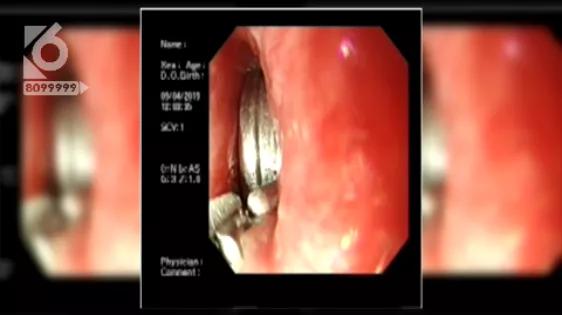

昆明市儿童医院 消化内科 段金涛:“从发现到我们医院一共是12小时左右,因为电池里面的化学物质,对孩子食道周围粘膜损伤比较明显,整个充血,水肿,糜烂都有。”

医生提供的图片可以看到,电池卡在孩子食道上,受唾液的浸泡,电池内的化学物质发生了渗漏,由于这些化学物质具有腐蚀性,虽然仅仅只是12小时,但孩子的食道已经被严重灼伤。

昆明市儿童医院 消化内科 段金涛: “观察以后觉得还是有胃镜取的条件,所以我们就在胃镜下进行了取出,同时及时的做了CT还提示孩子有食道穿孔。”